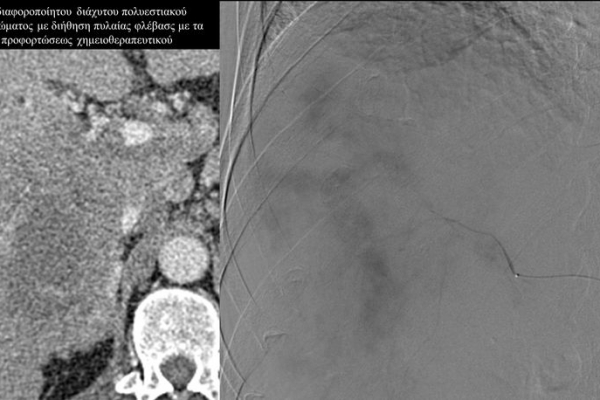

Ο χημειοεμβολισμός είναι μέθοδος τοπικής χημειοθεραπείας για πρωτοπαθή και δευτεροπαθή νεοπλάσματα του ήπατος. Σκοπός του είναι η τοπική έγχυση χημειοθεραπευτικού σε κλάδους της ηπατικής αρτηρίας, ώστε να επιτευχθούν υψηλές συγκεντρώσεις τοπικά στην ηπατική εξεργασία χωρίς να προκαλούνται οι συστηματικές επιπλοκές τοξικότητας του χημειοθεραπευτικού. Επιπλέον προκαλείται τοπική ισχαιμία στην περιοχή του όγκου από τα εμβολικά υλικά-μικροσφαιρίδια εμβολισμού.

Ενδείξειςαποτελούν επίσης το χολαγγειοκαρκίνωμα και οι μεταστάσεις από καρκίνο του μαστού, καρκίνωμα νεφρού και σαρκώματα μαλακών μορίων.